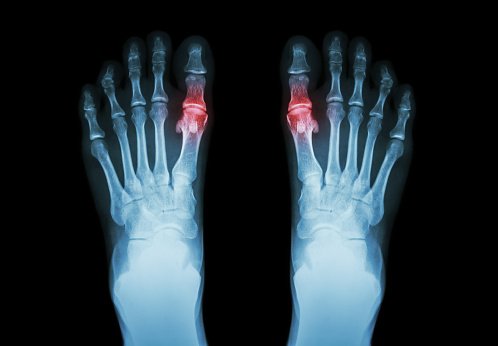

Diagnóstico y tratamiento de la hiperuricemia y la gota: revisión sistemática de las guías de práctica clínica y las declaraciones de consenso.

BMJ Open 2019Se necesitan mejoras en la calidad metodológica  de los documentos de orientación sobre gota e hiperuricemia. Falta evidencia para ciertas preguntas clínicas, a pesar de numerosos ensayos en este campo. Promover métodos de desarrollo de orientación estándar y sintetizar evidencia clínica de alta calidad son enfoques potenciales para reducir las inconsistencias de recomendación.

Hiperuricemia y tratamiento farmacológico de la gota

Butlletí d’informació terapèutica BIT. Vol. 30, núm. 2, 2019CatSalut, 10 de mayo de 2019Este Boletín revisa los tratamientos farmacológicos de los ataques agudos de gota y de la hiperuricemia haciendo un posicionamiento de los fármacos disponibles. Finalmente, se abordan diferentes controversias relacionadas con el tratamiento como el manejo de la hiperuricemia asintomática o la retirada del alopurinol.